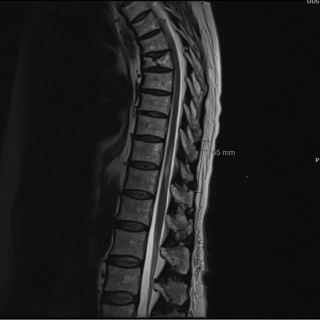

Denne kasuistikken beskriver alvorlig iatrogen botulisme etter behandling med injeksjon av botulinumtoksin ved en privatklinikk i utlandet. En kvinne i 40-årene ble akuttinnlagt i medisinsk avdeling grunnet økende svelgparese, svakhet i nakkemuskulatur, obstipasjon, munntørrhet, hodepine, fatigue, tunge øyelokk og uklart syn de siste fem dager. De siste tre dagene før innleggelsen hadde hun ikke fått i seg flytende eller fast føde, og hodet måtte støttes når hun skulle sette seg opp. Det fremkom at hun 15 dager tidligere hadde fått injisert botulinumtoksin type A mot migreneplager under et...